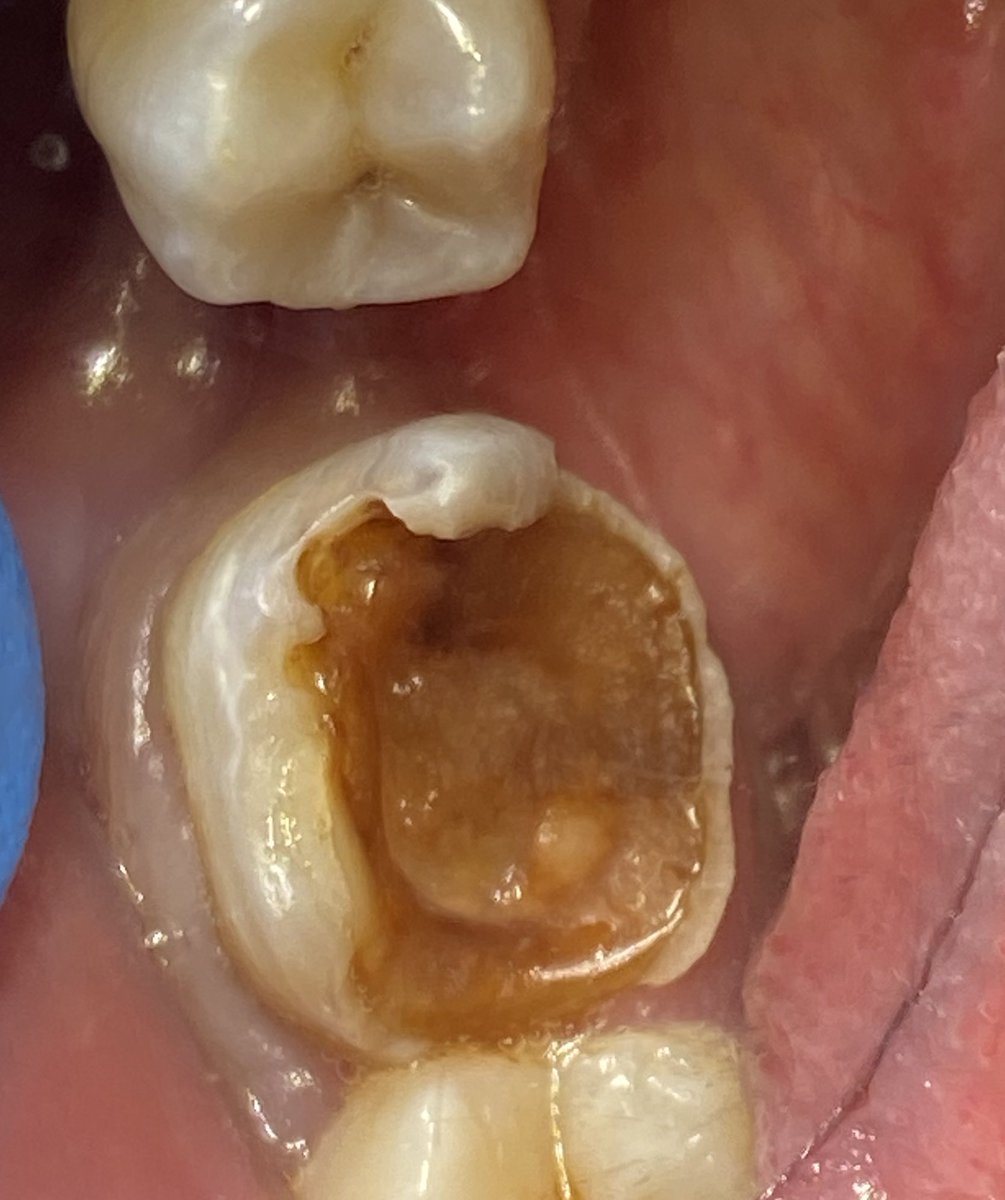

الضرس الثاني للمريض نخللللع ؟

حضر المريض بضرسين مقرره للخلع من كذا عياده وابلغته انه طبعا بالامكان المحافظه عليه وتم ذلك في جلسه واحده

هنا يوجد. Large PA lesion